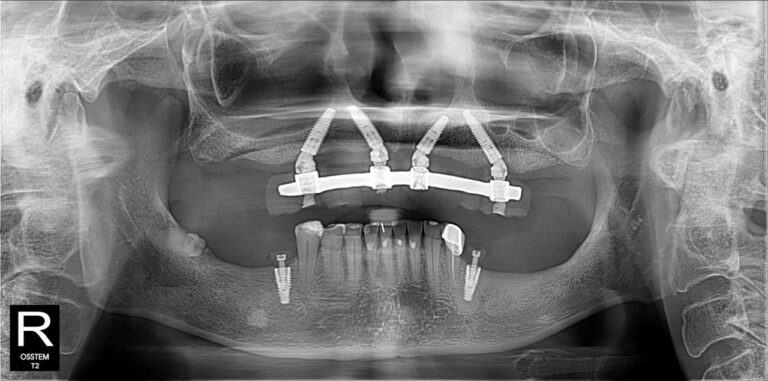

Không nằm ở lời nói mà thể hiện qua kết quả điều trị thực tế. Những hình ảnh X-quang dưới đây là sự khẳng định cho năng lực phẫu thuật và sự chính xác tuyệt đối của BS CKI Nguyễn Trung Khánh trong các ca đại phẫu thuật Implant nhiều lần cắm.